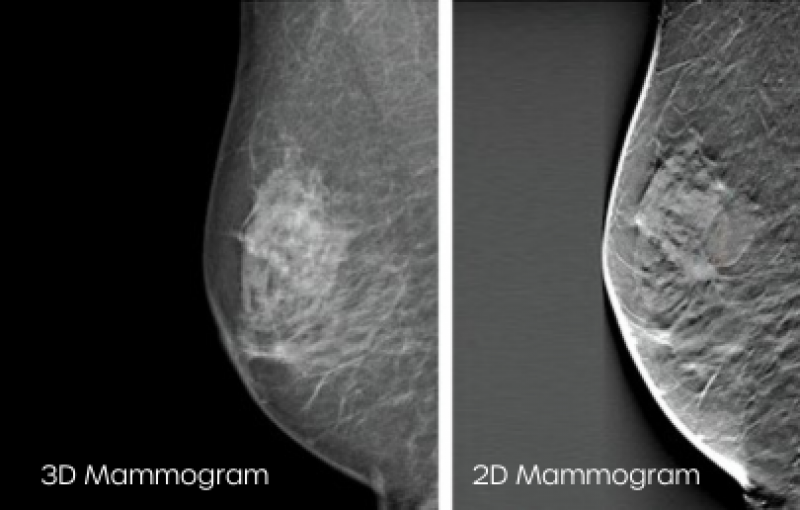

3D vs 2D

• Improved Detection: 3D tomosynthesis provides a detailed, multi-slice view of breast tissue, which helps in the early detection of breast cancer. The thin slices reduce overlapping breast tissue, which assists the Radiologist to better see through your breast tissue on the mammogram.

• Better Visualisation: 3D tomosynthesis allows radiologists to visualise breast tissue in a more comprehensive manner, making it easier to identify small tumours or other abnormalities. This can lead to earlier detection and more effective treatment.